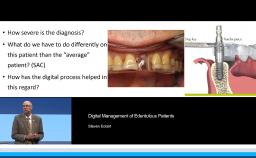

Ceramic materials are increasingly used for the fabrication of dental reconstructions. However, because there are so many options for fabricating ceramic prostheses, the selection of an ‘ideal’ material is becoming more and more complex. This lecture presents concepts for choosing the type of reconstruction, material, and method of fabrication for a highly esthetic outcome. Long-term survival rates, advantages, and limitations for new ceramic methods and materials - in particular high-strength ceramic zirconia - are presented in this lecture. The results of clinical studies comparing digital CAD/CAM and conventional workflows for fabrication of all-ceramic restorations are also presented.